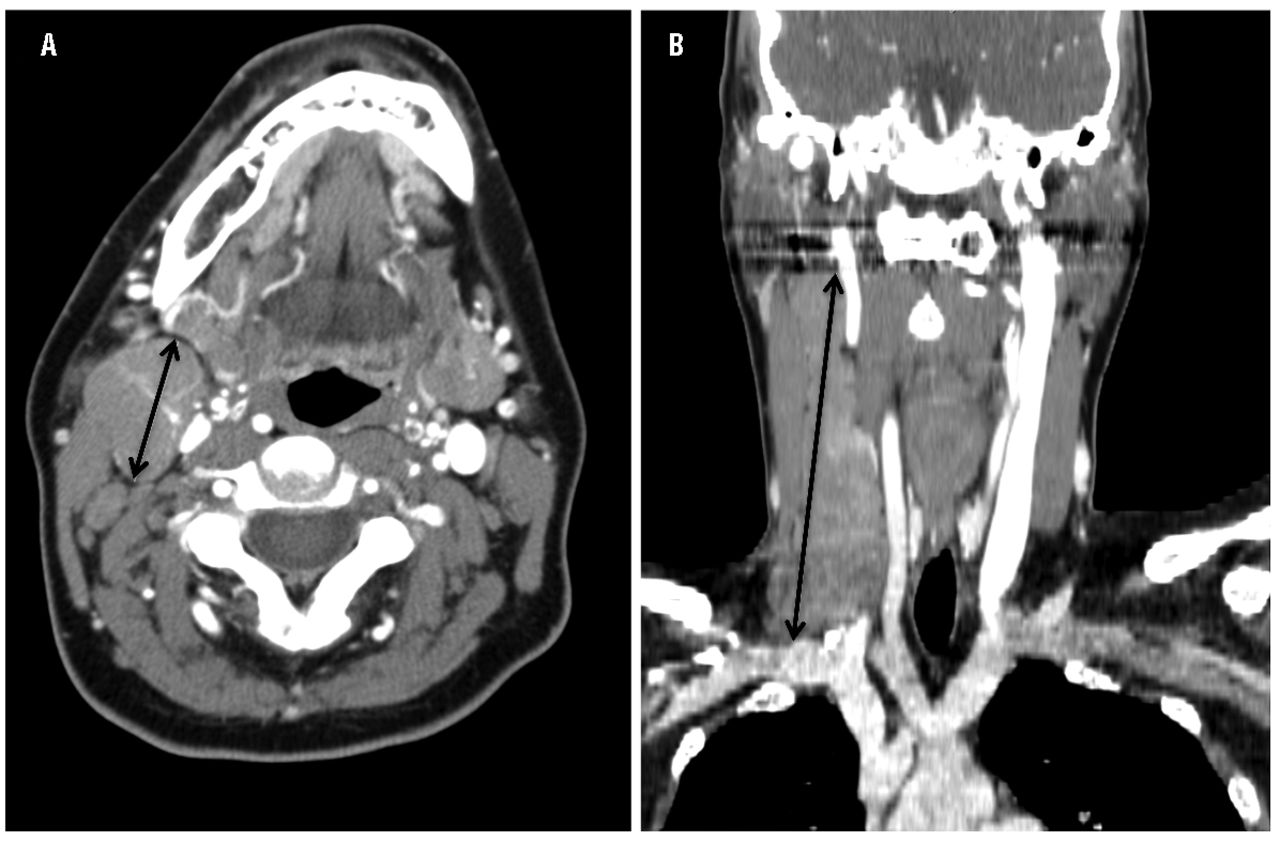

This retrospective analysis investigated the prognostic significance of bulky disease measured in transverse and coronal planes on computed tomography imaging. Chemotherapy treatment with ABVD doxorubicin bleomycin Velban and dacarbazine for 6 cycles. Smaller tumours often respond better to therapy than larger ones. The stage of your cancer. The extent to which the cancer has spread in the body. This retrospective analysis investigated the prognostic significance of bulky disease measured in transverse and coronal planes on computed tomography imaging. Bulky mediastinal Hodgkins disease management and prognosis. The Hodgkins lymphoma Stage IV prognosis is therefore reasonably positive. It is based on the following 7 unfavourable risk factors.